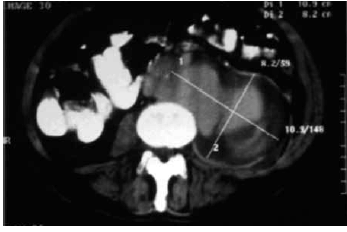

Homem, 63 anos, dislipidêmico e tabagista (50 maços/ ano), obeso, sem sintomas prévios, apresentou dor abdominal súbita e intensa, localizada em região do flanco esquerdo, irradiada para a região lombar esquerda, acompanhada de hipotensão arterial, sudorese e palidez, além de dor à elevação da coxa esquerda. Descompressão brusca abdominal negativa, palpação dificultada pelo abdome volumoso. Houve melhora da dor com analgésico, porém sem recuperação dos níveis pressóricos. Foi submetido à tomografia computadorizada de abdome, demonstrada na imagem.

Qual o diagnóstico provável e o tratamento indicado?